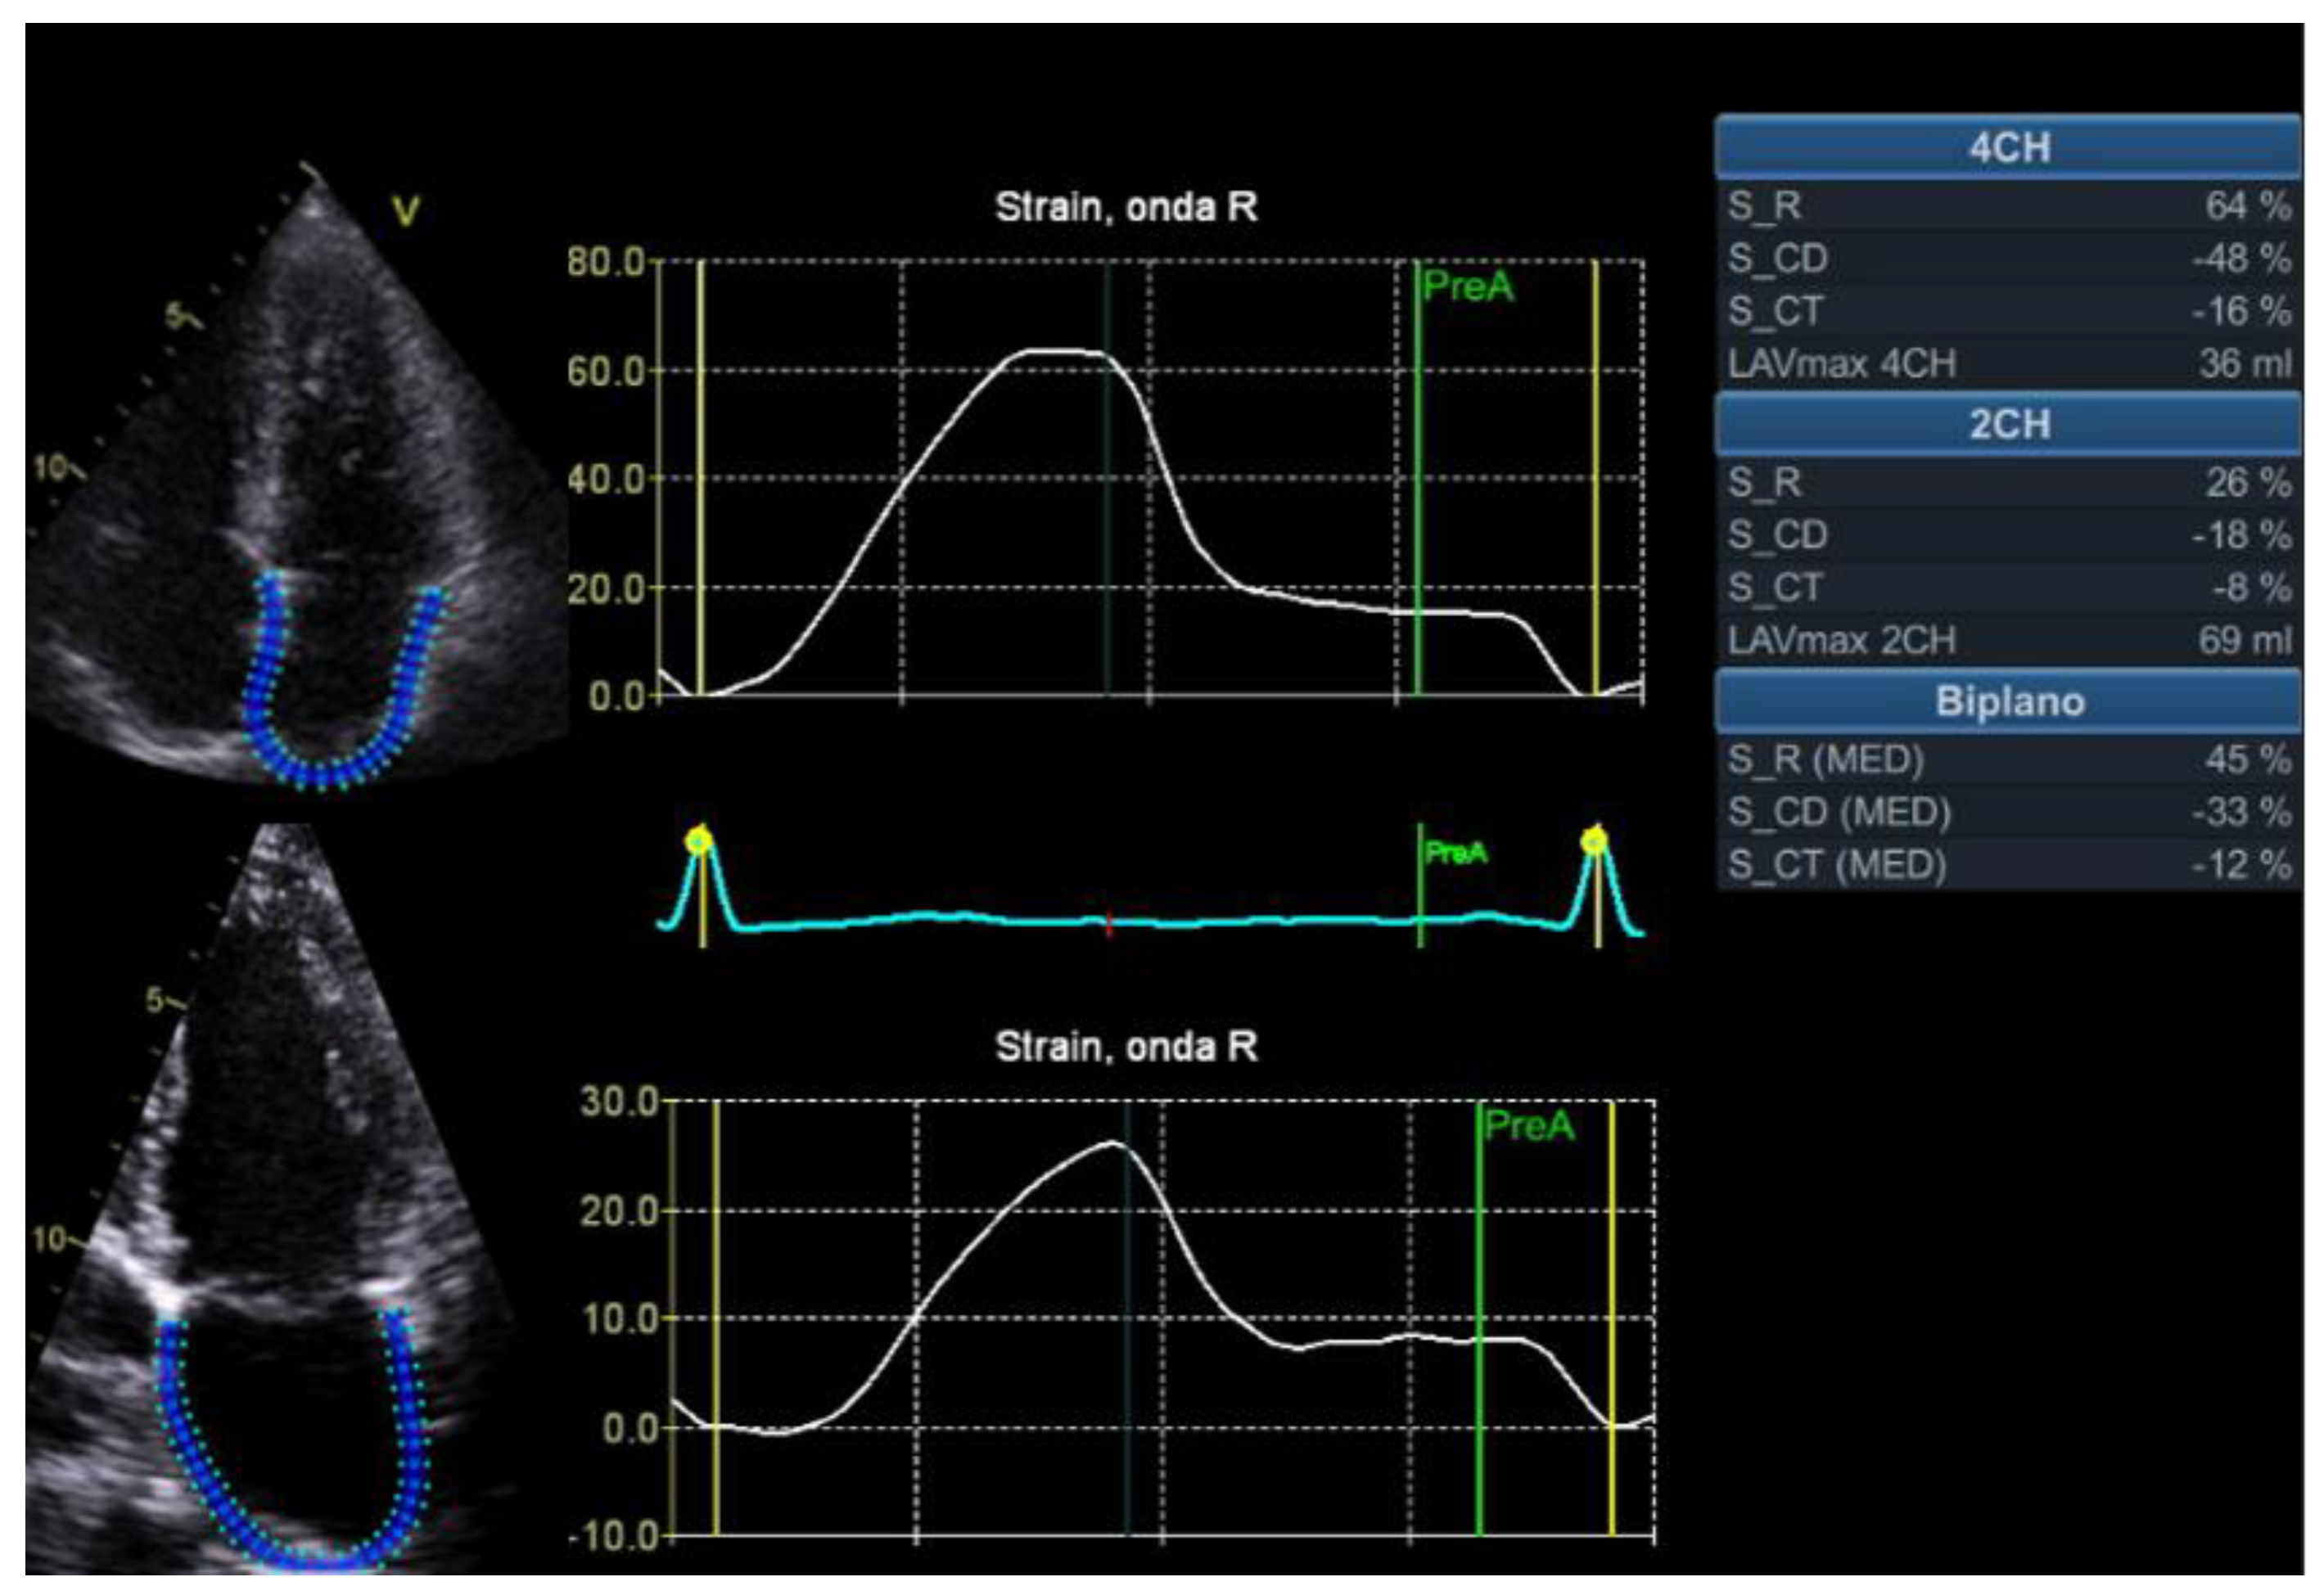

2. Global Longitudinal Strain

2.1.2. HFpEF